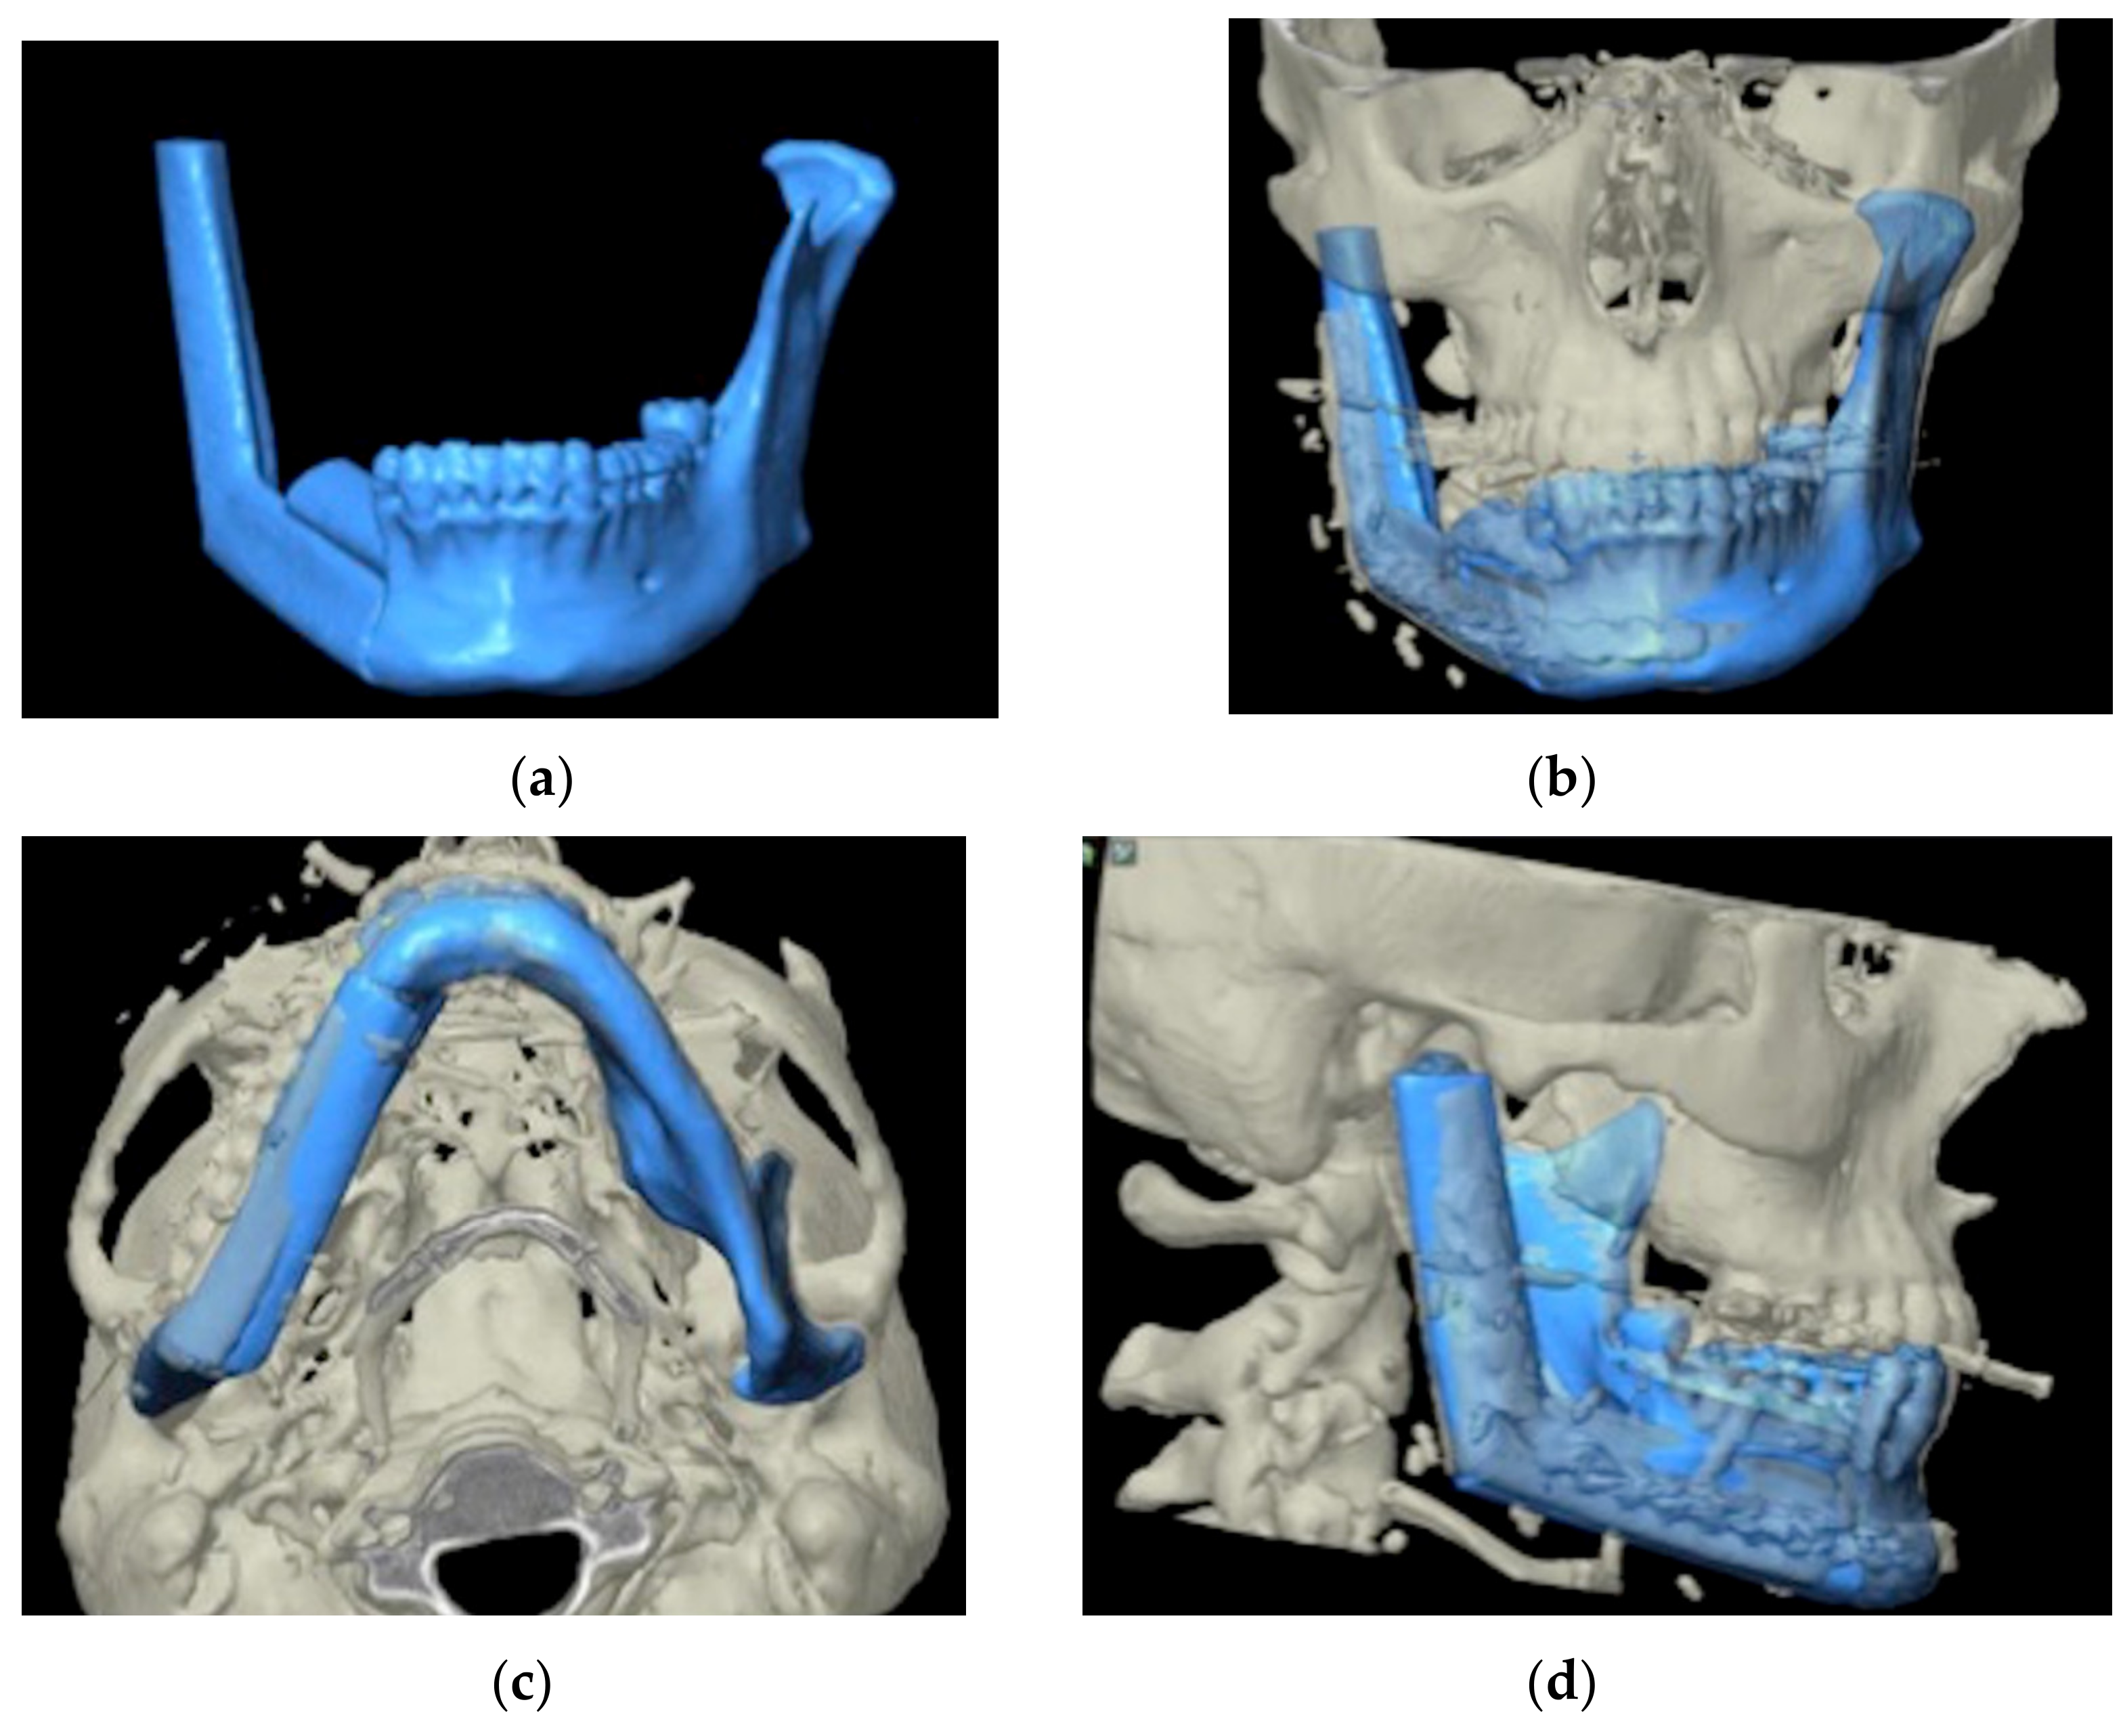

2.2. Virtual Planning

2.3. 3D Model Printing and Plate Shaping

2.4. Pre-Surgical Navigation: 3D Model Registration

2.5. Intra-Operative Surgical Navigation